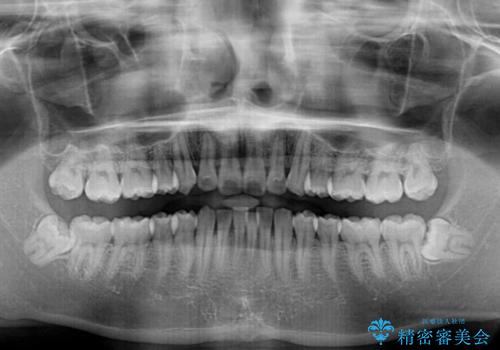

- 矯正治療の後戻りを気にして来院された患者様です。

後戻りは軽微であったので、インビザライン・ライトにより矯正治療を行うこととしました。

インビザライン・ライトは提供されるマウスピースの数に制限があり、通常のタイプよりもマウスピース提供期間が短くなっている一方、安価に治療を行うことができるプランです。

治療のゴールも変更できないため、軽微な歯列不正や、後戻り改善などに適しています。

矯正治療後は、再度後戻りすることを極力回避するために、下顎前歯の舌側を細いワイヤーを用いて保定することとしました。